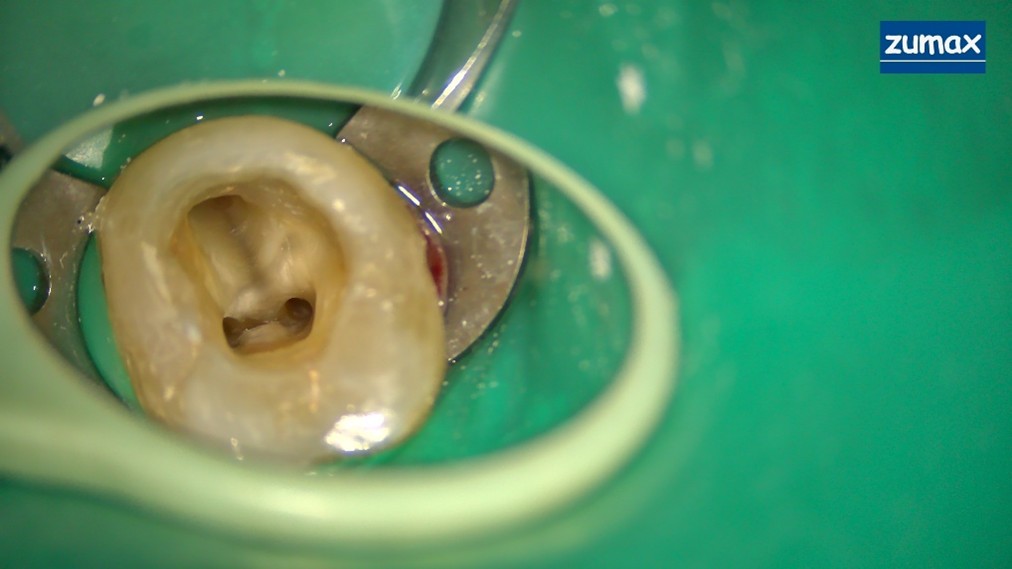

MICROSCOPIC PICTURE :

MESIAL CANALS

MESIAL AND DISTAL CANALS

The dental operating microscope provided significant advantages during treatment:>

• 1.Better visualization helped reduce excessive dentin removal

• 2.Confirmation of complete pulp chamber debridement

• 3.Improved ability to locate the canals

• Microscopic images of mesial canals

• Microscopic images of mesial and distal canals

• Images captured during the obturation step